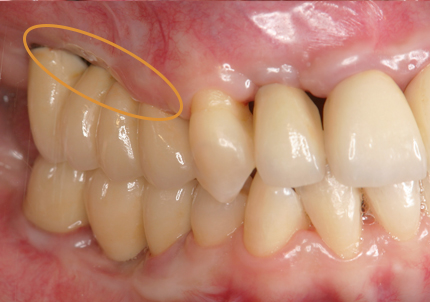

1.初診時口腔内(2007年6月30日)

3.右上インプラント補綴物装着(2009年7月24日)

↑ 右上サイナスリフト後にインプラント埋入

4.左上下7番インプラント補綴物装着(2010年5月24日)

5.右上7番インプラント(2013年11月6日)

6.右下6,7番インプラント(2017年9月15日)

7.左上6番インプラント(2021年2月21日)

8.初診より現在に至る

強い歯ぎしり、くいしばりで奥歯の歯牙破折、深い虫歯で保存不可能となり全顎治療となる。

↑ 2025年9月9日

治療後は経過良好